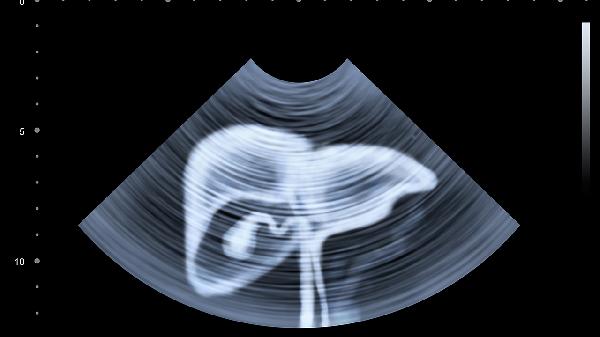

肝硬化、心力衰竭等疾病会导致腹腔积液。特征为腹部对称性膨大伴移动性浊音,可能伴随下肢水肿。需通过超声检查确诊,治疗需针对原发病进行。

育龄期女性出现进行性腹部增大伴停经,多为正常妊娠表现。子宫随孕周增大超出盆腔,可通过尿妊娠试验和B超确认。需注意与假性妊娠等病理情况鉴别。